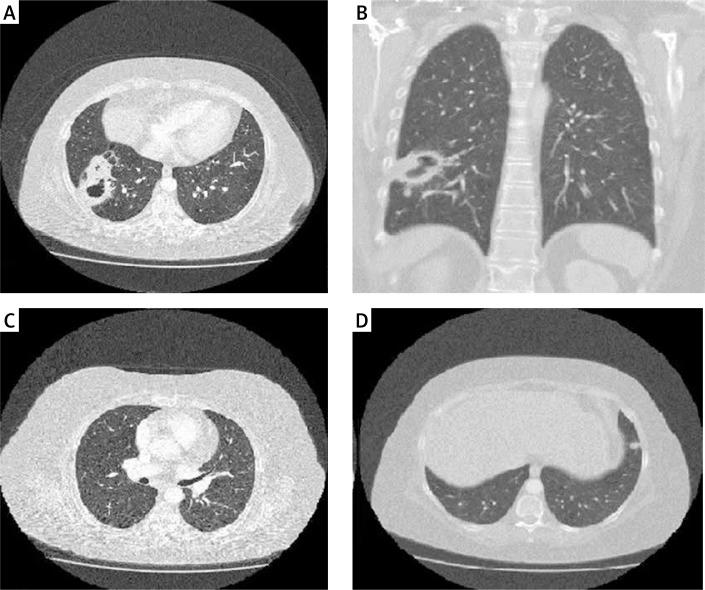

多发性肺类风湿结节。

Multiple pulmonary rheumatoid nodules.

We present a case of 45-year-old female patient with the diagnosis of seropositive rheumatoid arthritis, who was admitted to our rheumatology department with exacerbation of the disease. The patient's disease activity score (DAS 28) was 6.9. Physical examination revealed changes in the lung auscultation as a rough breathing sound at the middle and lower lobe of the right lung. Chest X-ray revealed multiple nodular densities in both lungs. Lung biopsy was performed for the diagnosis and revealed necrotizing granulomas with central fibrinoid necrosis surrounded by epithelioid cells. Such a histopathological picture is typical for rheumatoid nodules. Finally the patient was treated with rituximab, with significant improvement.

我们报告一例45岁血清阳性类风湿关节炎女性患者,因病情加重入住我院风湿科。患者的疾病活动评分(DAS 28)为6.9。体格检查发现肺部听诊有变化,右肺中、下叶呼吸音粗糙。胸部X线显示双肺多发结节状密度影。为明确诊断进行了肺活检,结果显示坏死性肉芽肿,中央为纤维蛋白样坏死,周围是上皮样细胞。这种组织病理学表现是类风湿结节的典型表现。最后患者接受了利妥昔单抗治疗,病情显著改善。